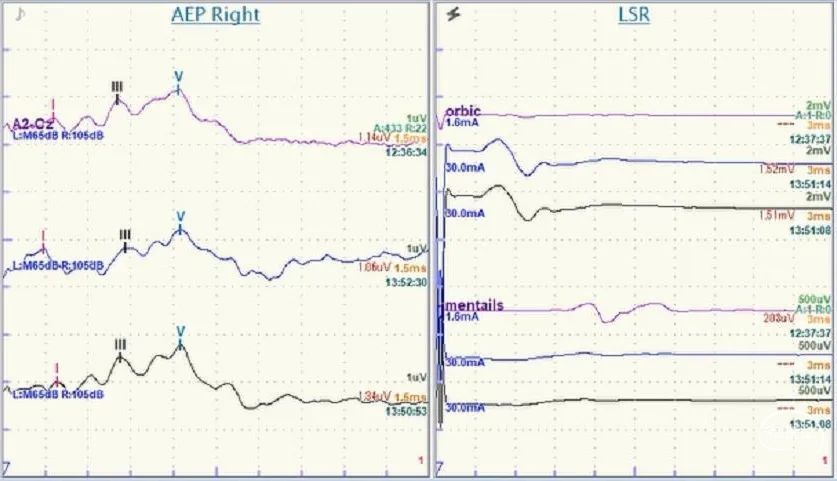

主要包括侧方扩散反应LSR、脑干听觉诱发电位BAEP等。

1.侧方扩散反应

侧方扩散反应(Lateral Spread Response, LSR)又称为异常肌反应(Abnormal Muscle Response,AMR)是面肌痉挛特有的电生理表现。即刺激面神经的一个分支导致另一个分支所支配的肌肉发生抽动。潜伏期一般为10ms左右。

▼基本原理

由于在HFS中面神经功能亢进,刺激面神经的一个分支(下图,刺激颧支或颞支)不仅诱发一个来自该条分支支配肌肉(下图,眼轮匝肌)的反应波,刺激还会逆行经面神经纤维传入,在REZ区经过责任血管壁交感神经桥接或神经纤维之间短路(目前尚无定论),传导到其他面神经分支纤维(下图,下颌缘支),在其他面部肌肉(下图,颏肌)记录到一个相对延迟10ms的的反应波(LSR 下图)。

减压后(下图),只能记录到来自被刺激分支支配肌肉(下图,眼轮匝肌)的反应波,刺激无法在REZ区传导到其他面神经分支纤维,LSR会消失(下图)。

BAEP(Brainstem Auditory Evoked Potentials)可反映整个听觉传导通路功能,在有条件的单位建议术中监测BAEP。

主要观察Ⅰ、Ⅲ、Ⅴ波。Ⅴ波的潜伏期被认为是监测听力受损的最好的指标,进行性的大于基线1.0~1.5ms的潜伏期延长或波幅变化大于50%(尤其是突然的变化)均应立即停止手术操作并查找原因。但BAEP无法实时监测蜗神经功能,当术中发现BAEP变化时,有时神经功能已无法恢复。

术中神经电生理监测:刺激颞支(或颧支),在颏肌记录;刺激下颌缘支,在眼轮匝肌记录。有条件的单位建议术中监测BAEP。